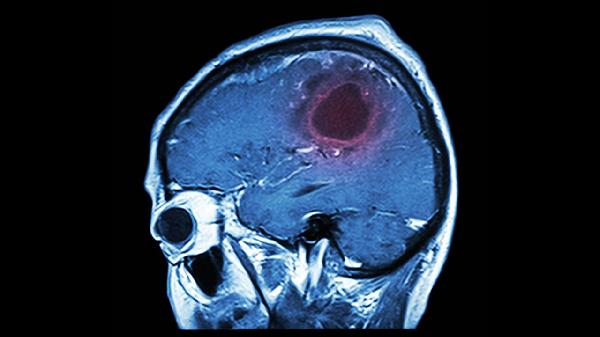

40岁以上人群应每年进行健康检查,重点关注血压、血糖、血脂等指标。脑血管高危人群可通过颈动脉超声、头颅CT等检查评估血管状况。发现脑血管畸形或动脉瘤时应及时就医,必要时进行手术治疗。